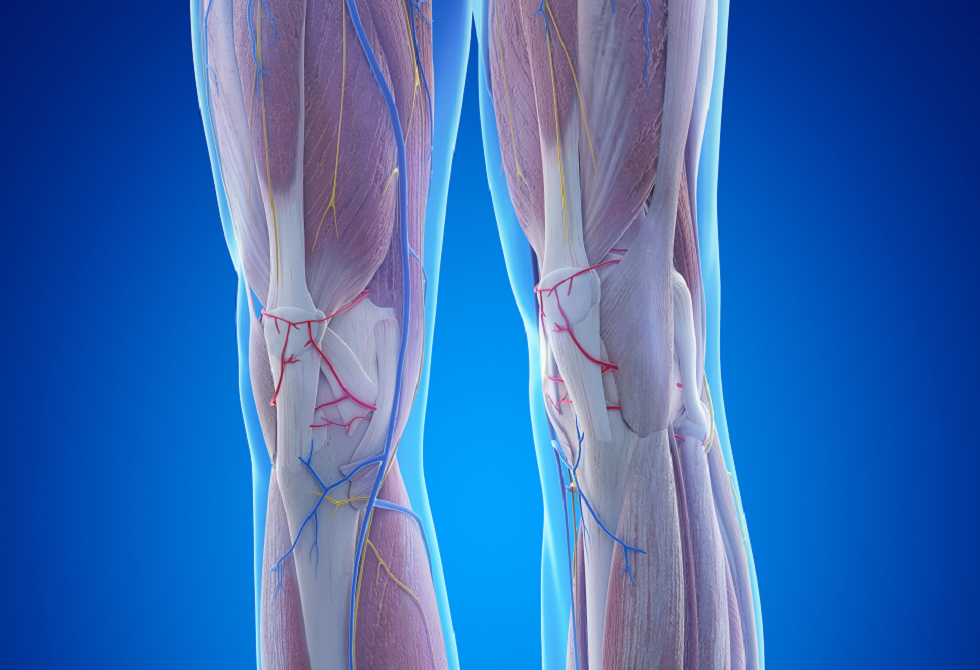

عامل خفي في العضلات قد يزيد خطر فقدان الأطراف

تكشف دراسة علمية جديدة أن ضعف العضلات لدى مرضى الشرايين المحيطية قد لا يرتبط فقط بضعف تدفق الدم، بل أيضا بتراكم الدهون داخل العضلات نفسها.

وقد يفسّر هذا العامل استمرار ضعف القدرة على المشي لدى كثير من المرضى حتى بعد العلاج.

ويعدّ مرض الشرايين المحيطية اضطرابا وعائيا يصيب أكثر من 200 مليون شخص حول العالم، ويتسبب في تضيق شرايين الساق غالبا نتيجة تراكم اللويحات داخل الأوعية الدموية. ومع انخفاض تدفق الدم، يعاني المرضى عادة من ألم في الساق، خصوصا أثناء المشي.

وفي المراحل المتقدمة من المرض قد يتطور الوضع إلى ما يعرف بنقص التروية المزمن المهدّد للأطراف، وهو انخفاض حاد في تدفق الدم قد يؤدي في النهاية إلى بتر الطرف المصاب.

ولسنوات طويلة ركّزت العلاجات المتاحة على إعادة فتح الشرايين وتحسين تدفق الدم، سواء عبر الجراحة أو من خلال تحفيز نمو أوعية دموية جديدة. إلا أن كثيرا من المرضى يظلون يعانون ضعفا عضليا شديدا حتى بعد نجاح هذه الإجراءات.

وفي دراسة حديثة، وجد باحثون من جامعة فلوريدا أن تراكم الدهون داخل العضلات الهيكلية — على غرار التبقّع الدهني في شريحة اللحم — يؤثر مباشرة في قدرة العضلات على العمل لدى المرضى المصابين بمراحل متقدمة من المرض.

ويشير الباحثون إلى أن هذه الدهون داخل العضلات ليست مجرد نتيجة لمرض الأوعية الدموية، بل قد تكون أحد الأسباب المباشرة لضعف الأطراف.

وقال الدكتور تيرينس رايان، الأستاذ المشارك في قسم علم وظائف الأعضاء التطبيقي وعلم الحركة في جامعة فلوريدا، إن الخيارات العلاجية المتاحة حاليا لمساعدة المرضى على تحسين قدرتهم على المشي ما تزال محدودة.

وأضاف أن العلاجات الحالية تركز أساسا على تحسين تدفق الدم، لكنها لا تعالج مشكلة تراكم الدهون داخل العضلات، ما يستدعي دراسة العوامل التي تؤثر في وظيفة الساق بصورة أدق وتطوير أساليب علاجية جديدة.

وعند تحليل عينات من عضلات الساق لدى مرضى يعانون تضيقا متقدما في الشرايين، لاحظ الباحثون أن الجينات المسؤولة عن تكوين الخلايا الدهنية كانت أكثر نشاطا بكثير مقارنة بالأشخاص غير المصابين بالمرض.

وأوضح الدكتور دانيال كوبينك، الأستاذ المشارك في قسم علم الأدوية والعلاجات بكلية الطب في جامعة فلوريدا، أن زيادة الدهون داخل أنسجة العضلات ترتبط بتراجع أداء العضلات.

وللتأكد مما إذا كانت الدهون سببا في هذا الضعف أم نتيجة له، أجرى الباحثون تجارب على الفئران، فقيّموا وظائف العضلات ونسبة الدهون داخلها. وأظهرت النتائج أن العضلات تصبح أضعف بوضوح عندما تتراكم فيها الدهون، حتى في حال استعادة تدفق الدم الطبيعي.

كما لاحظ الباحثون أن تعديل العملية التي تنظم بها بعض البروتينات إنتاج الدهون أدى إلى تحسن أداء العضلات، حتى دون تغيير تدفق الدم إلى الأطراف.

وتشير هذه النتائج إلى أن بنية العضلات نفسها قد تلعب دورا مهما في تطور المرض، وهو ما يفتح المجال أمام نهج علاجي مختلف لا يقتصر على الشرايين فقط، بل يستهدف أيضا منع تراكم الدهون داخل العضلات.

ويأمل الباحثون أن تساهم الدراسات المستقبلية في تحديد العوامل التي تدفع إلى تراكم الدهون في عضلات الساق لدى المرضى الذين يعانون ضعف تدفق الدم، بما يساعد على تطوير علاجات تحسن قوة العضلات والقدرة على المشي، وتنعكس إيجابا على جودة حياة المرضى.

نشرت الدراسة في مجلة Circulation.